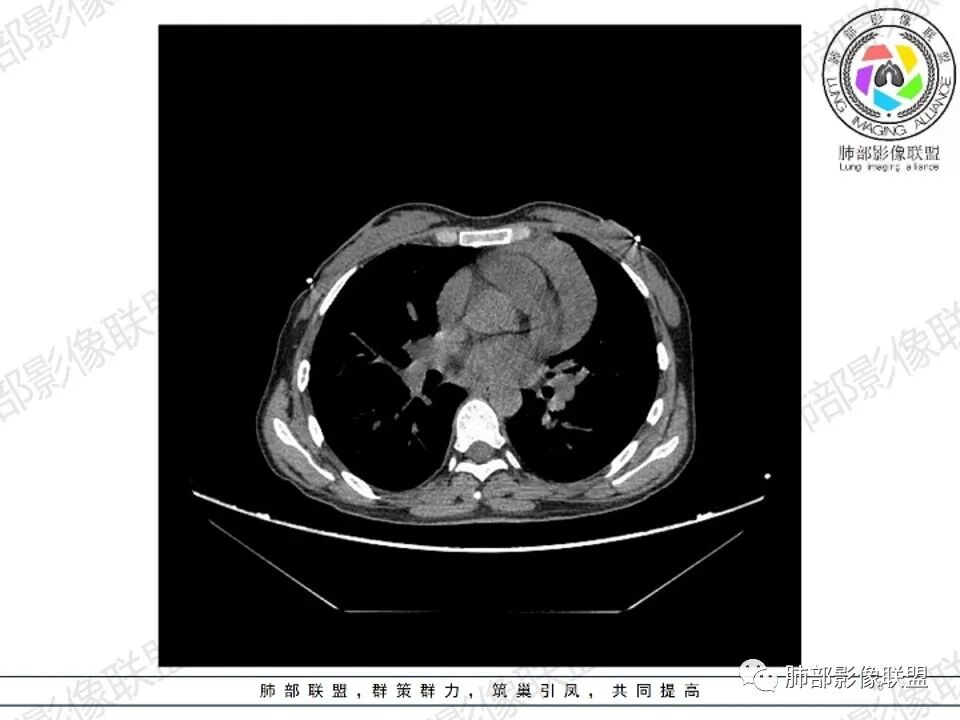

年轻女性 前中纵隔多发肿块,质软,相互融合,向下侵及心包。增强不均匀强化,内见血管影。双侧腋下多组淋巴结肿大。考虑恶性,淋巴瘤,胸腺瘤。

纵隔多发结节堆积 塑型生长  质软 边界不清 强化不均  双侧腋窝淋巴结肿大

年轻女性,贫血,CT示前纵隔团片状软组织占位,多结节堆积感,塑形生长,边界欠清,包绕大血管及心包,增强明显不均匀强化,内见血管漂浮。纵隔4R,5,7区及双侧腋窝多发肿大淋巴结,综合考虑为淋巴瘤可能

病灶两叶,相对独立,中央相连

整体还是胸腺的形态

边缘平直为主,稍膨隆,但是无明显的局限性凸起

囊变区域弥漫,大部分直达壁,分界不清,部分分界清楚

内部血管走形自然

多发淋巴结肿大

女,27,间断头晕、乏力3年,左眼视物模糊2月。贫血。胸部CT:前纵隔不规则肿块,多结节融合,边界不清,沿主动脉及肺动脉间隙生长,平扫密度欠均匀,增强扫描可见多发低密度坏死,纵隔血管供血穿行,腋窝多发大小不等淋巴结肿大。考虑恶性病变,胸腺癌?肉瘤?淋巴瘤?鉴别胸腺瘤、结节病等。

2.影像显示前纵隔不规则块状影,依势贴附心脏大血管旁,密度不均,边界不甚清楚,有结节融合感。

3.病灶轻度不均匀强化,可见血管穿行,散在液性低密度区。

双肺门未见肿大淋巴结。

4.双侧腋窝区见增大淋巴结,边界清楚。